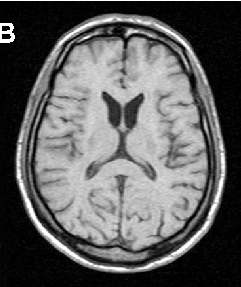

Huntington’s Disease-like 2

HDL2 presents usually in young adulthood, but, as with HD, the age of onset is inversely related to the size of the trinucleotide repeat expansion (Table 2) [30]. Patients may develop psychiatric abnormalities as the initial manifestation, with later appearance of chorea, parkinsonism and dystonia [14]. The disease may evolve from chorea to a more bradykinetic, dystonic phenotype, or remain parkinsonian throughout the disease course, but unlike HD, this is not related to the size of the trinucleotide expansion. Unlike in ChAc and MLS, deep tendon reflexes are usually

brisk; there are no peripheral nerve or muscle abnormalities, and seizures have not been reported. Acanthocytosis is found in about 10% of HDL2 patients and CK levels are normal. Neuroimaging reveals bilateral striatal atrophy, in particular of the caudate nucleus. In contrast to ChAc and MLS, generalized cortical atrophy may develop during the disease course. Neuropathologically, ubiquitin-immunoreactive intranuclear neuronal inclusions, similar to those seen in HD, are found [30].

In ChAc and MLS, electroneurography may demonstrate sensorimotor axonal neuropathy whereas electromyography may show neurogenic as well as myopathic alterations. Electroencephalographic findings are not specific and may comprise normal findings, generalized slowing, focal slowing, and epileptiform discharges. Neuroradiologically, there is progressive striatal atrophy especially affecting the head of caudate nucleus and impaired striatal glucose metabolism similar to that seen in HD (Figure 2) [24,26]. Voxel-based morphometry of MRI scans in ChAc shows specific involvement of the head of the caudate nucleus [41,42]. Neurodegeneration in both core NA syndromes affects predominantly the caudate nucleus, putamen and globus pallidus. In ChAc, thalamus and substantia nigra are also involved. In contrast to HD, there is no significant cortical pathology [8,43-45]. Neuropathological findings consist of neuronal loss and gliosis of variable degree in these regions, but no inclusion bodies of any nature or other distinct neuropathological features have as yet been detected.

Cerebral MRI is often diagnostic in PKAN, and the diagnosis is confirmed by analysis of the PANK2 gene (Figure 2). Analysis of the JPH3 gene CTG expansion is useful in patients of African ancestry with suspected HDL2.

A B

C D

E F

G H

Figure 2 Neuroimaging. ChAc. Coronal FLAIR- (A) and axial T1-weighted (B) images demonstrate moderate atrophy of the caudate nucleus. MLS. Axial T2-weighted images demonstrate moderate atrophy of caudate nucleus and putamen (C) but no relevant cortical atrophy (D). HDL2. Axial FLAIR- (E) and coronal T1-weighted images (F) demonstrate atrophy of the caudate nucleus and the fronto-temporal cortex. In addition, FLAIR images show periventricular white matter hyperintensities (courtesy of Nora Chan, MD, UCLA, Los Angeles, USA). PKAN. T2-weighted fast spin echo (G) and T1-weighted (H) brain MRI scans from a child with PKAN demonstrating the “eye of the tiger” sign (courtesy of Susan J. Hayflick, MD, Oregon Health and Science University, Portland, Oregon, USA)